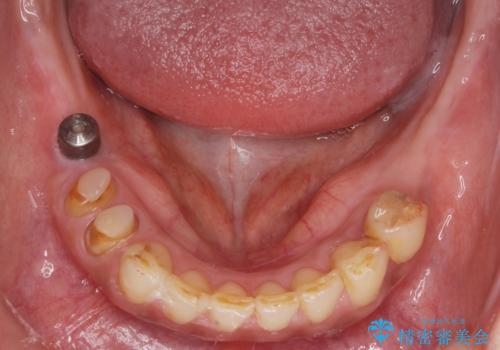

痛くて噛めない インプラントで全て治療したい

- 痛くて噛めない、これまでだましだまし治療をしてきたがこれを機にすべてきっちりと治したい、口の中の悩みを解決したいと来院されました。

抜歯や歯周病治療、欠損補綴を含め、全顎的な治療を計画・提案します。

インプラント治療の注意事項(リスク・副作用など)

- 外科手術のため、術後に痛みや腫れ、違和感を伴います

- メンテナンスを怠ったり喫煙により、お口の中に大きな悪影響を及ぼすインプラント周囲炎等にかかる可能性があります

- 糖尿病、肝硬変、心臓病等の場合、インプラント治療ができない可能性があります

- 高血圧、貧血・不整脈等の場合、インプラント治療後に治癒不全を招く可能性があります

- 自費診療(保険適用外治療)となります